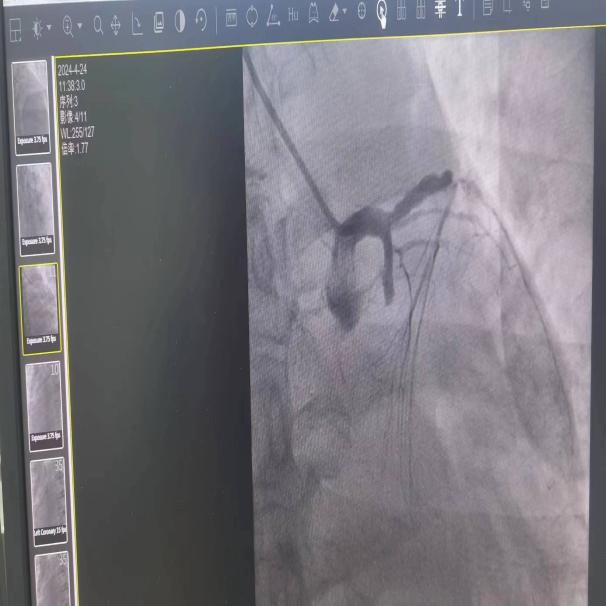

未开通血管